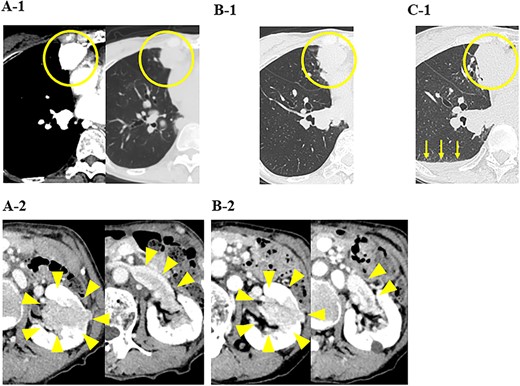

Ten months after the start of lenvatinib, CT showed a decrease in the sizes of pulmonary metastases (Fig. 3A) and renal metastasis (Fig. 3B) (tumor reduction rate: 45%). Remnant thyroid resection was performed and followed by RAI therapy with 100 mCi. In 131I scintigraphy, some lung metastases showed radioiodine uptake, whereas others did not. Radioiodine uptake was also observed in the left renal tumor, but not in the right kidney (Fig. 4A); therefore, the left renal tumor was finally confirmed as renal metastasis of PTC. Since the sizes of pulmonary and renal metastases both increased after the RAI therapy (tumor growth rate: 71%) (Fig. 4B), the administration of lenvatinib was resumed from a dose of 4 mg/day. After resuming lenvatinib, she has been in SD status for 6 months.

CT images of the chest and abdomen 10 months after the start of the administration of lenvatinib, and (A) pulmonary metastases decreased in size; (B) the size of the renal tumor decreased and the tumor plug disappeared.

In the present case, the patient was diagnosed as RCC with multiple pulmonary metastases, and the administration of nivolumab and ipilimumab was initiated. In our hospital, since the size of pulmonary metastasis rapidly increased, it was challenging to perform complete thyroidectomy followed by whole-body RAI scanning. Because lenvatinib was expected to be effective for both RCC and pulmonary metastasis of PTC, the administration of lenvatinib was started. And lenvatinib, which inhibits angiogenesis, was expected to be effective against metastatic lesions, which were very hypervascular on contrast-enhanced CT. The administration of lenvatinib provided long-term disease control and it was possible to perform remnant thyroid resection as well as whole-body RAI scanning. Based on which the renal tumor was diagnosed as metastasis of papillary thyroid carcinoma.